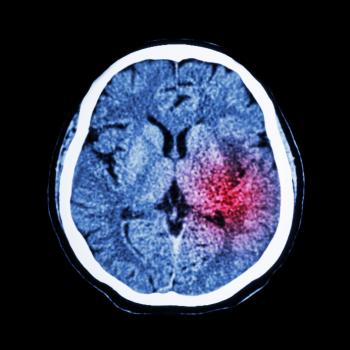

缺血性中风是最常见的情势,约占所有中风的87%。它在含氧丰富的动脉血流向大脑受阻时发生,主要是由于血凝块堵塞。

出血性中风约占所有中风的13%,是因为脑血管渗漏或破裂引起的。

中风究竟会对人造成怎样的影响取决于中风发生在大脑中的哪一个侧面以及它造成损伤的量。比如,有些人可能会出现暂时性的手臂或腿部无力,而其他人可能会失去说话或走路的能力。